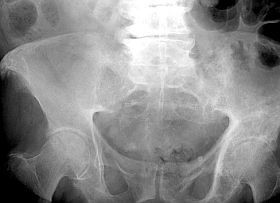

A Paget-kórt a daganatszerű csontelváltozásokhoz sorolják. Habár inkább csontanyagcsere betegségének tartják, sokan a csontdaganatok közt is megemlítik, mert egyrészt megjelenése alapján nehéz elkülöníteni a valódi csontdaganatoktól, másrészt az esetek egy részében rosszindulatú csontdaganatok alakulhatnak ki belőle. Férfiakban gyakoribb, általában 30-40 éves korban jelentkezik.

A tünetek és a fizikai vizsgálat alapján sejteni lehet a diagnózist. A diagnózis megerősítése egyrészt röntgenfelvételekkel történik, melyeken jól láthatók a betegségre jellemző kóros csontelváltozások, másrészt laborvizsgálattal, mely a csontsejtek képződésében szerepet játszó enzim, az alkalikus foszfatáz vérszintjét mérik.